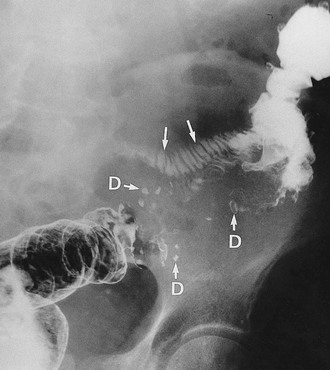

Diverticular disease occasionally presents with large bowel obstruction due to acute inflammatory thickening, muscle hypertrophy and spasm. Incomplete obstruction is more common and presents as severe constipation. Chronic diverticular inflammation sometimes causes local fibrous strictures, particularly in the sigmoid, which cause intermittent bouts of constipation when the stool is dry. When detected radiologically or endoscopically, these strictures must be distinguished from malignancy or Crohn's disease by biopsy (Figs. 29.5 and 29.7).

Ischaemic colitis is a condition of the elderly which usually presents with rectal bleeding. The history is characteristic; there is a bout of cramp-like abdominal pain lasting a few hours, followed by an attack of rectal bleeding. Usually the bleeding is dark red, often without faeces, and occurs one to three times over about 12 hours. The episode then ceases spontaneously. The differential diagnosis includes acute bleeding from diverticular disease. The cause is transient ischaemia of a segment of large bowel, followed by sloughing of the mucosa with the splenic flexure the most vulnerable. Further attacks occasionally occur but most patients have no further trouble. Investigation by barium enema in the acute stage may reveal colonic oedema in the affected segment (see Fig. 29.9). A rare late complication is fibrotic stricturing of the area affected by ischaemia.